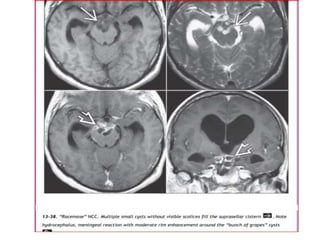

LOCATION

• T. solium larvae are most common in

the CNS, eyes, muscles, and

subcutaneous tissue. The intracranial

subarachnoid spaces are the most

common CNS site, followed by the

brain parenchyma and ventricles

(fourth > third > lateral ventricles)